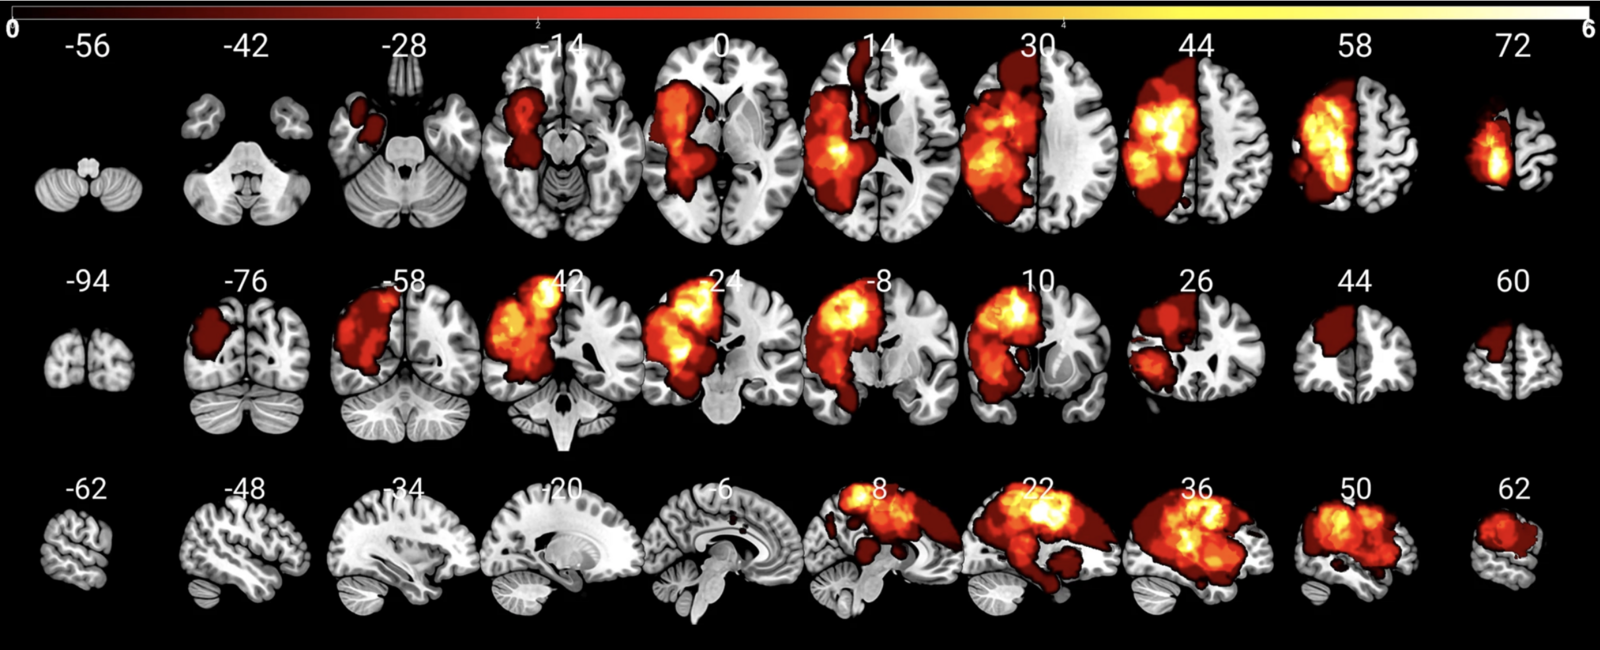

Distribution of the patients’ lesions. Copyright: Lucius Fekonja

Lesion overlay map of brain tumor patients, Copyright: Lucius Fekonja

Brain Networks and Language Function

Latest Research Results by MoA Members Published in the Renowned Journal »Cortex«

Cutting | Symbolic Material | Brain | Publications MoA researchers have succeeded in determining more precisely the relation between certain brain networks and language function. The interdisciplinary team investigated language dysfunction on a voxel level using the voxel-lesion-symptom-mapping method in glioma patients. Among the contributors are MoA members Lucius Fekonja (Scientific Visualization) and

Thomas Picht (Digital Neurosurgery) from the Image Guidance Lab at Charité Berlin and Friedemann Pulvermüller (Neuroscience, Linguistics, and Psychology) and Felix Dreyer (Linguistics and Brain Research) from the

Brain Language Laboratory at Freie Universität Berlin

.